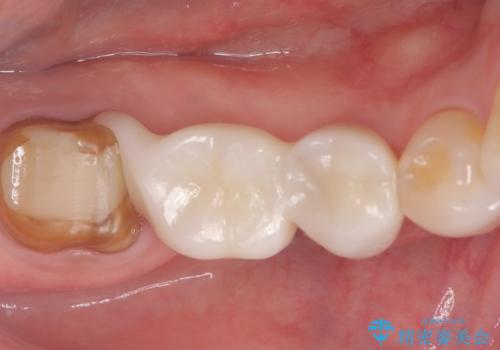

健全歯質の残存量から、クラウンでのやり替えを提案しオールセラミッククラウン(スタンダード)でのやり替えとなりました。

・オールセラミッククラウン(スタンダード) 121,000円(税込み)

・仮歯 11,000円(税込み)